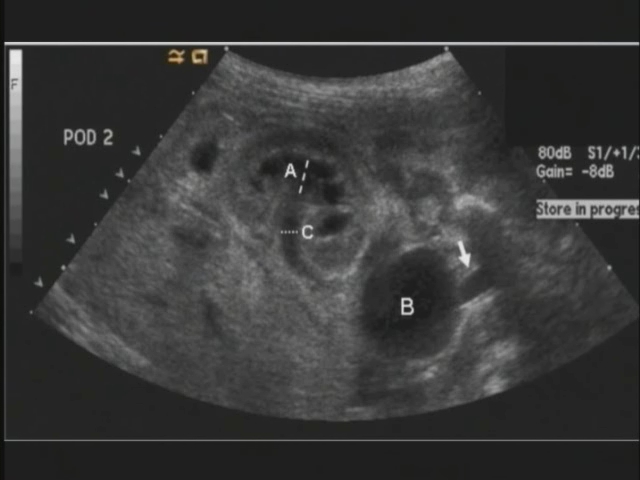

The Mitrofanoff Procedure: R..

The Mitrofanoff Procedure: R..

Carlo Passerotti, MD; David A. Diamond, MD; Alan B. Retik, MD; Hiep T. Nguyen, MD / CINE-MED